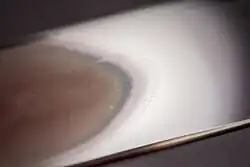

![]() Two push-type peripheral blood smears suitable for characterization of cellular blood elements. Left smear is unstained, right smear is stained with Wright-Giemsa stain. | |

A blood smear is made by placing a drop of blood on one end of a slide, and using a spreader slide to disperse the blood over the slide's length. The aim is to get a region, called a monolayer, where the cells are spaced far enough apart to be counted and differentiated. The monolayer is found in the "feathered edge" created by the spreader slide as it draws the blood forward.